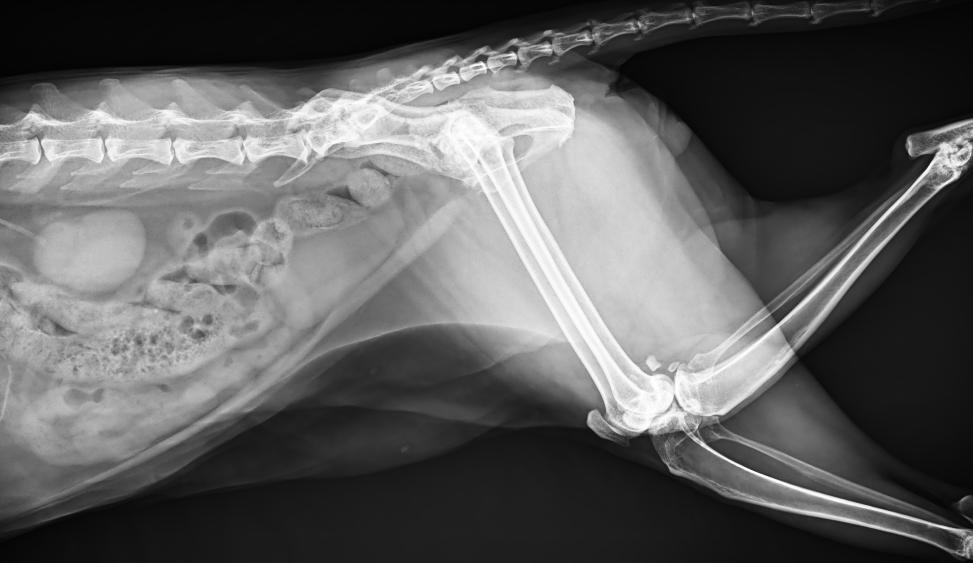

● 17*17大尺寸平板探測器,獲得高質量圖像

● 優(yōu)異的空間分辨率及信噪比,提升圖像質量

● 采用線噪聲消除技術,使成像質量提升40%

● 智能高效的圖像處理軟件,大幅提升圖像質量